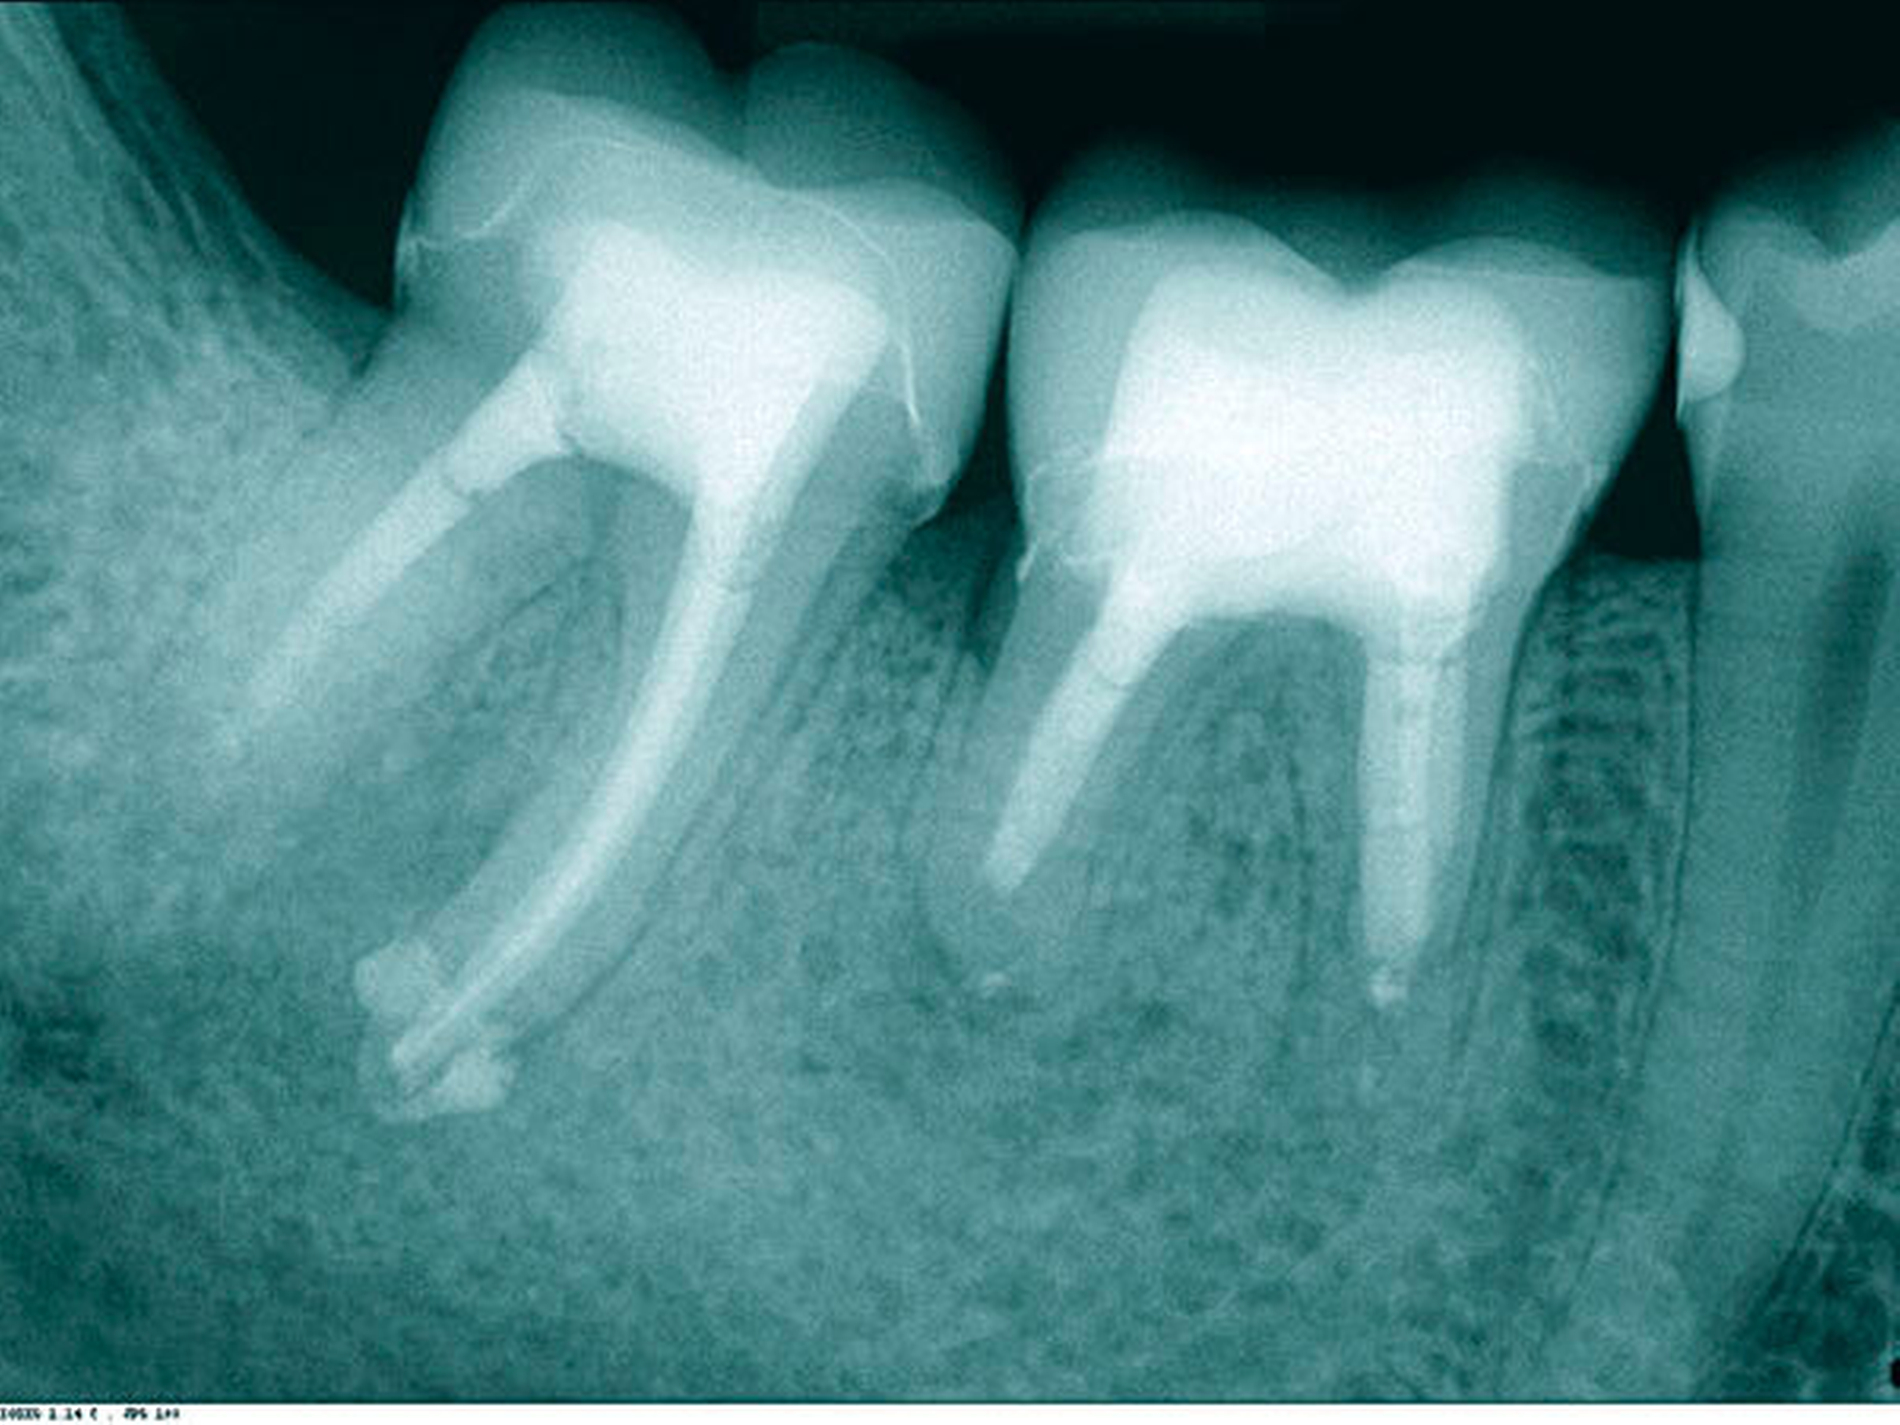

In der ersten Therapiesitzung erfolgte – nach Isolierung mit Kofferdam – die Trepanation des Zahnes und die Stiftentfernung mit Ultraschallinstrumenten. Im Anschluss wurden die drei gefüllten Kanäle revidiert, der vierte, nicht abgefüllte, mesiobukkale Kanal dargestellt und präpariert. Die elektronische Längenmessung ergab 14,5 mm für den mesiobukkalen Kanal, 17,0 mm für den mesiolingualen, 15 mm für den distobukkalen und 16 mm für den distolingualen. Aufgrund der großen initialen Kanaldurchmesser und der guten Einsicht bis ins periapikale Gewebe (Abbildung 2) wurde auf eine Längenmessaufnahme verzichtet. Die Desinfektion erfolgte mit Natriumhypochlorid (NaOCl) 5 Prozent und EDTA 17 Prozent, sowie Schallaktivierung mittels EDDY-Spitzen (VDW, München). Das Wurzelkanalsystems wurde manuell mit K-Feilen bis IS0 70 präpariert. Es folgte eine medikamentöse Einlage mit AH Temp (DentsplySirona, Bensheim). Danach wurde eine Aufnahme zur Kontrolle der vollständigen Guttapercha-Entfernung und der suffizienten Einbringtiefe des Kalziumhydroxids angefertigt (Abbildung 3).